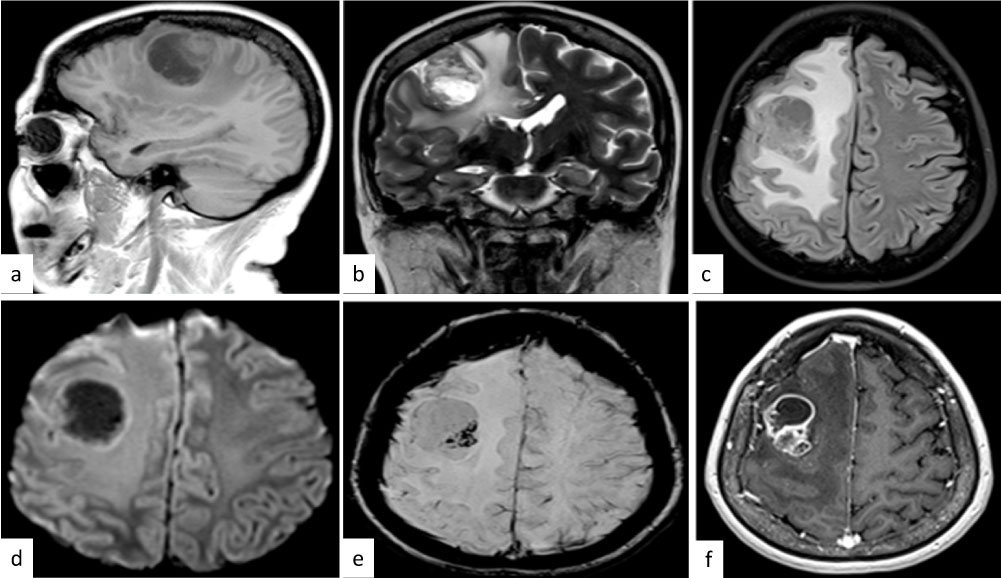

Physical examination revealed no abnormality, with a normal neurological examination. Magnetic resonance imaging (MRI) scan showed a hypodense area in the right temporal region, with marked enhancement in the medial parts and severe surrounding brain edema (Figure 1).

Figure 1: Radiologically imagines. (a), (b) and (c). MRI showed a brain tumor with hypodense area in the right temporal region (d), (e) and (f) with marked enhancement in the medial parts and severe surrounding brain edema. View Figure 1